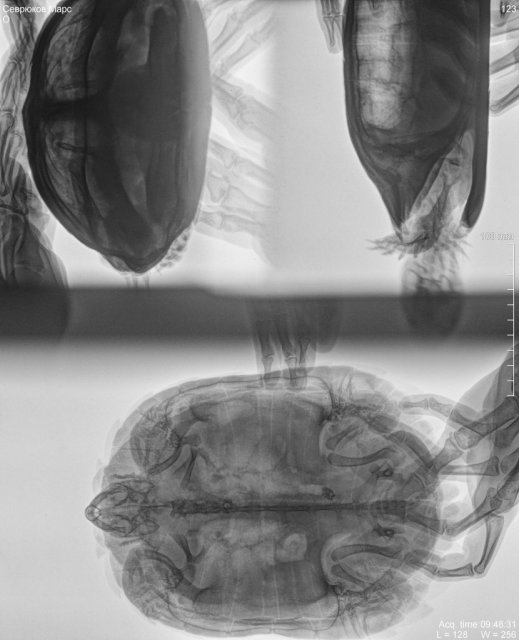

Вам нужно обязательно сделать ей рентген. Такой грунт при поедании имеет свойство накапливаться и постепенно забивать жкт. Т.е. сначала никаких проблем визуально нет, но достигнув критической массы это всё приводит к кишечной непроходимости. Поэтому в первую очередь рентген.

Что Вам нужно на приёме - рентген, желательно в двух проекциях, обязательно под номером 1 и любую из 2 и 3. Лёгкие видно только в проекциях 2 и 3. Если сделает только 1 и будет говорить про пневмонию - не видно по ней лёгкие, вообще никак.

Сделали рентген. Фото ниже.

Врача герпетолога сегодня в клинике не было. Будет на месте только послезавтра. Постараюсь через отзывы найти другие клиники.

Рентген сделали до кормления, прямо с самого утра. После рентгена есть опять отказался (лась). Не съел(а) ни одного кусочка. Возможно из-за стресса после поездки к врачу.

Добавляю фото в другом контрасте.

Т.к. врача-герпетолога не месте не было, а был только рентгенолог снимки сделали обычные, без ввода каких либо контрастирующих препаратов.

@shalim наш врач снимки посмотрела - она не видит признаков закупорки, поэтому её состояние не из-за лавы и нужно искать причину в другом